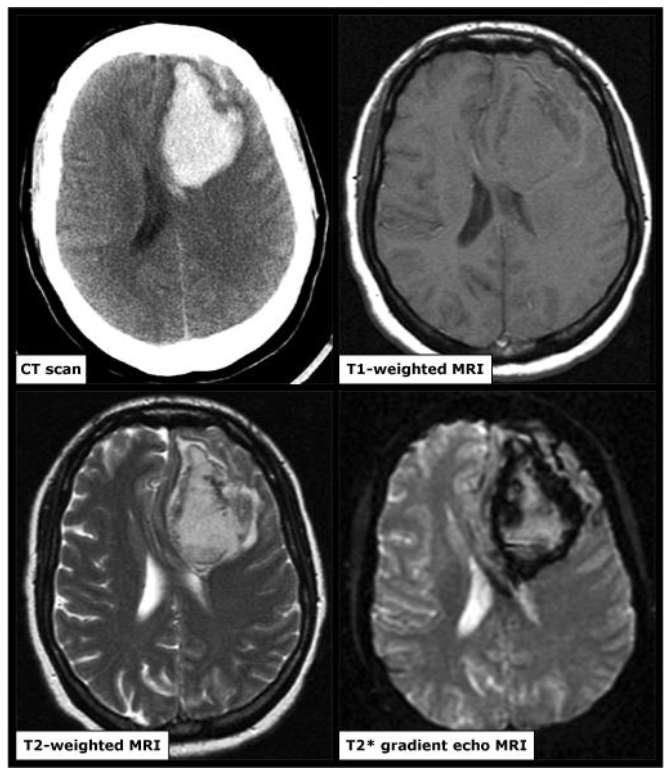

Chụp cộng hưởng từ(MRA) sọ não

Cộng hưởng từ (MRA) có độ nhạy để chẩn đoán xuất huyết não tương đương với CT sọ não không tiêm thuốc cản quang. MRA có thể phát hiện các nguyên nhân gây xuất huyết não như các u não chảy máu hay nhồi máu chuyển dạng chảy máu. Ở các bệnh nhân suy thận hay dị ứng thuốc cản quang thì việc đánh giá mạch não có thể thực hiện được thông qua MRA mạch máu mà không cần tiêm chất tương phản. Tuy nhiên, do giá thành cao, việc thăm khám kéo dài và tính khả dụng thấp hơn CT sọ não nên MRA ít khi được sử dụng để chẩn đoán xuất huyết não trong bệnh cảnh cấp cứu.

Hình ảnh xuất huyết não trên MRA có thể đặt ra nhiều thách thức do biểu hiện của máu thay đổi theo các chuỗi xung, thời gian kể từ lúc bắt đầu chảy máu, kích thước và vị trí chảy máu.